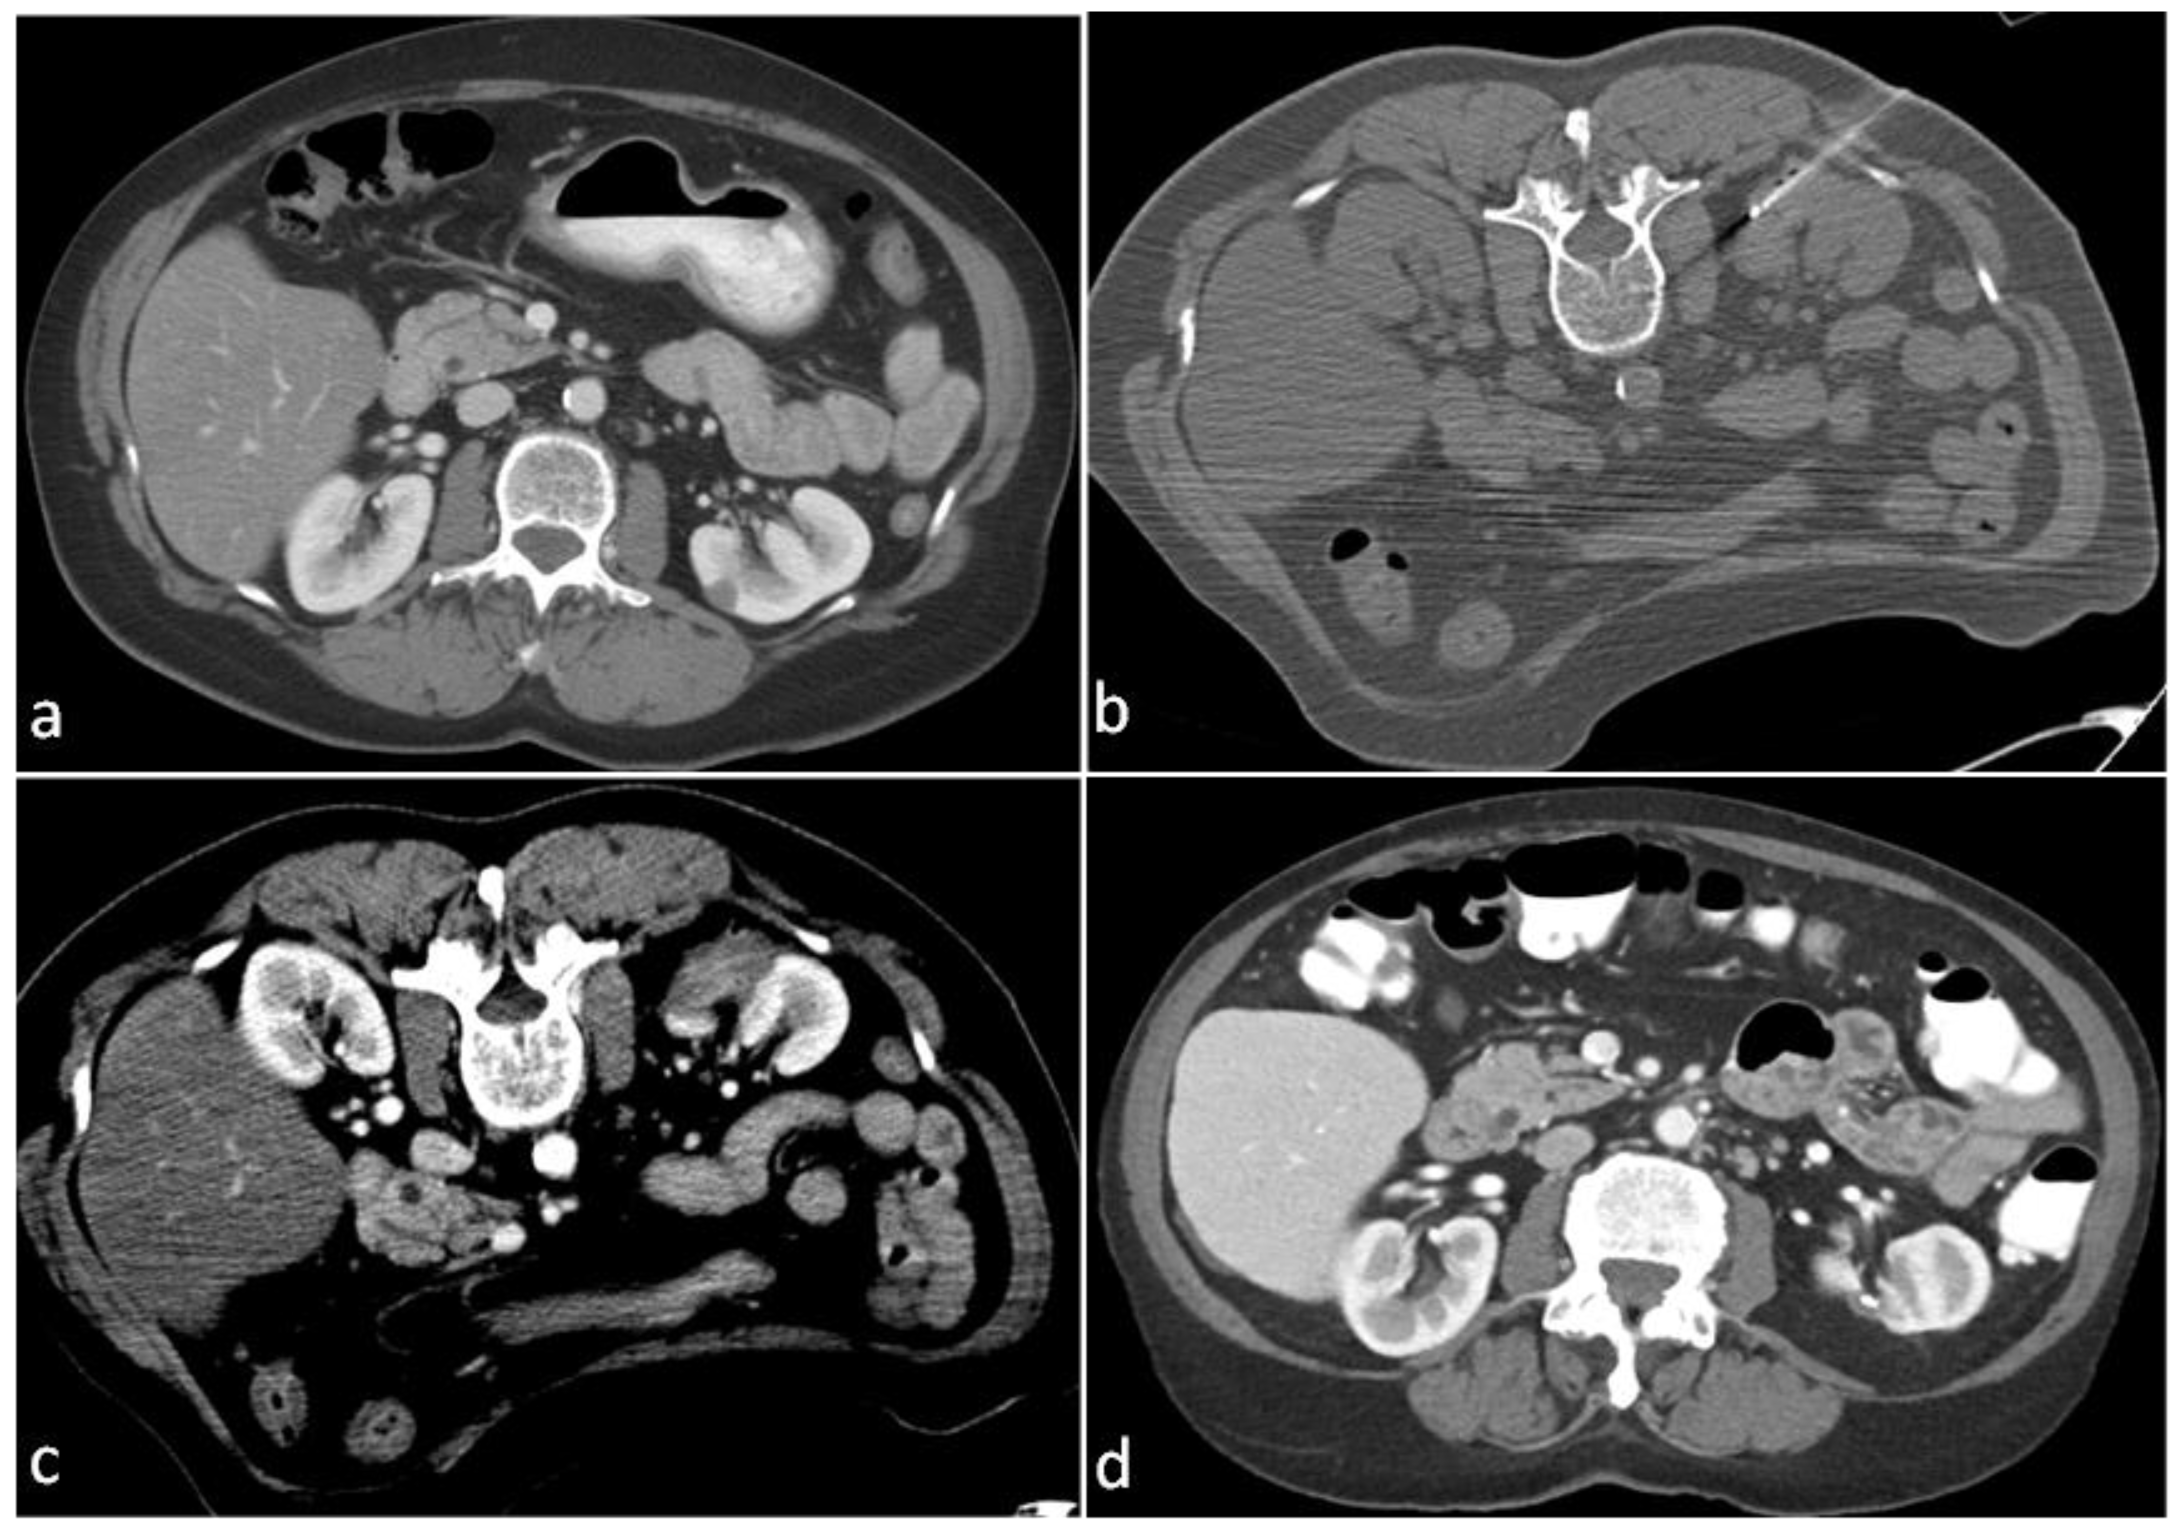

2.1. Ablation Technique